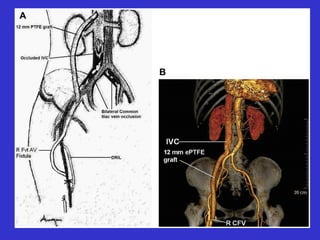

“ A well performed fistulogram is the

foundation for all percutaneous interventions ”

Thorough evaluation of the entire vascular access circuit

including the graft, native veins, and inflow arteries

Diagnostic Fistulogram

21 g butterfly needle

non-ionic contrast

multiple venous stenoses